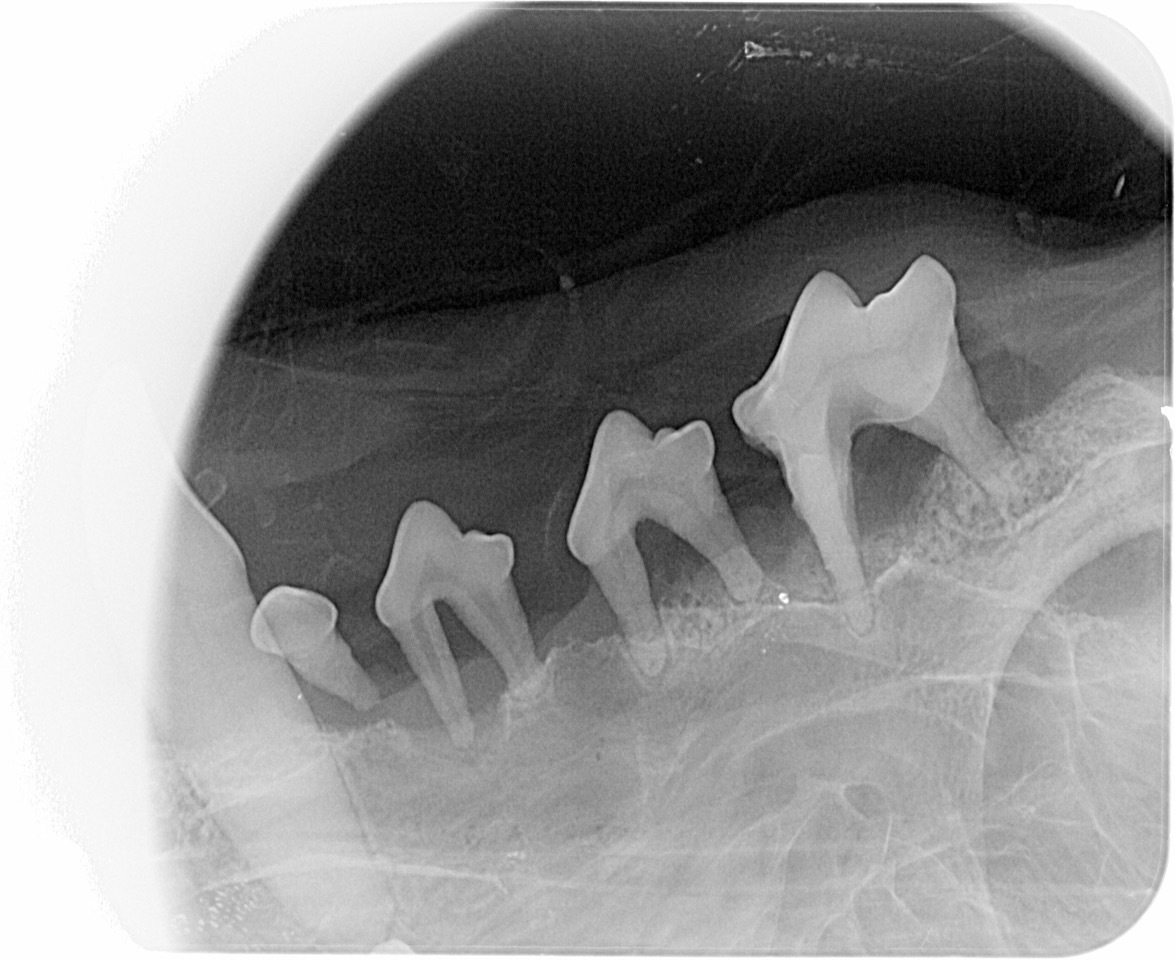

In aller Gemütsruhe können die Bakterien ihr zerstörerisches Werk fortsetzen. Zahnfleisch ist dann schon lange nicht mehr interessant, jetzt kommt der Knochen dran. Die Zähne werden locker, der Halteapparat macht schlapp und die Hunde verlieren ihre Zähne im günstigsten Fall. Der Fachausdruck für diese Erkrankung heißt Parodontitis. Häufig jedoch sind die erwähnten Taschen eitrig infiziert, der Zahnstein hält alles zusammen, der Hund stinkt aus dem Maul und darf nicht mehr auf die Couch. Spätestens jetzt hängt der Haussegen schief! Hier hilft nur noch eine professionelle Zahnreinigung durch Ihren Tierarzt mit ultraschallgeführter Beseitigung des Zahnsteins, parodontologischer Untersuchung der Zähne mittels Sonde, röntgenologischer Untersuchung des Wurzelapparates, Spülung und Säuberung der vorhandenen Taschen, Extraktion der hoffnungslosen Fälle und Politur der verbliebenen Zähne (Bilder 1-3). Dies funktioniert nur richtig in Vollnarkose! Aber so weit muss es gar nicht kommen. Das sollte möglichst nur Plan B sein!